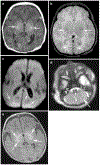

Background: Deep nuclear gray matter injury in neonatal hypoxic-ischemic encephalopathy (HIE) is associated with worse neurodevelopmental outcomes. We previously published a qualitative MRI injury scoring system utilizing serial T1-weighted, T2-weighted and diffusion-weighted imaging (DWI), weighted for deep nuclear gray matter injury.

Materials and methods: MRI scans from neonates with moderate to severe HIE treated with therapeutic hypothermia were evaluated. Signal abnormality was scored on T1-weighted, T2-weighted and DWI sequences and assessed using an established system in five regions: (a) subcortical: caudate nucleus, globus pallidus and putamen, thalamus and the posterior limb of the internal capsule; (b) white matter; (c) cortex, (d) cerebellum and (e) brainstem. MRI injury was graded as none, mild, moderate or severe. Inter-rater reliability was tested on a subset of scans by two independent and blinded neuroradiologists. Surviving infants underwent the Bayley Scales of Infant and Toddler Development-III (Bayley-III) at 18-24 months. Data were analyzed using univariate and multivariate linear and logistic regression.

Results: Fifty-seven eligible neonates underwent at least one MRI scan in the first 2 weeks of life. Mean postnatal age at scan 1 was 4±2 days in 50/57 (88%) neonates and 48/54 (89%) surviving infants underwent scan 2 at 10±2 days. In 54/57 (95%) survivors, higher MRI injury grades were significantly associated with worse outcomes in the cognitive, motor and language domains of the Bayley-III.

Conclusion: A qualitative MRI injury scoring system weighted for deep nuclear gray matter injury is a significant predictor of neurodevelopmental outcome at 18-24 months in neonates with HIE.